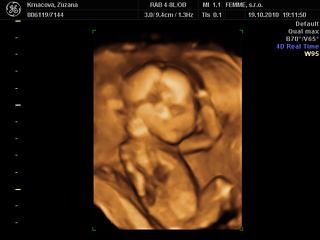

@petasllov no nas doktor nam vypocil termin na 2. april, ale po 3D a morfologii stale ultrazvuk vyhodil 1.4, ale nevadi ak to bude aj na den blaznov, hlavne nech je zdravi ved vynimka potvrdzuje pravidlo 😀 , aspon nikto nezabudne na jeho narodeniny 😵 a rodinu sme dopredu varovali, ze ak si malinky vyberie 1.4 termin a budeme im volat nech to neberu ako 1. aprilovy zart 😝